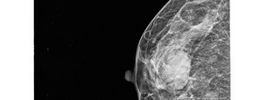

Mammography -Breast Tumor